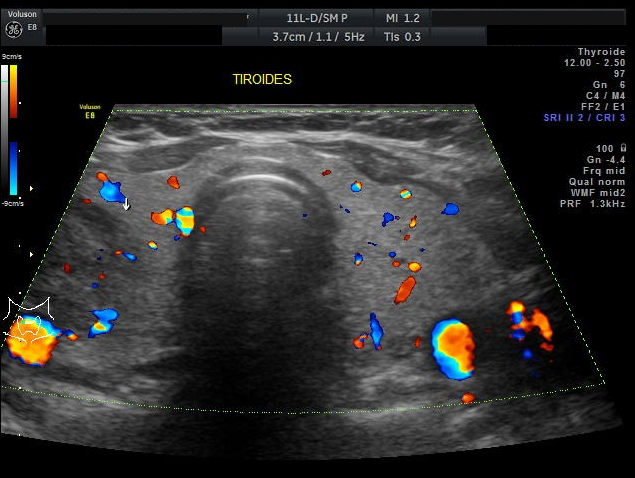

Una vez revisados los nuevos paraclínicos, la paciente es mantenida con la misma dosificación de Levotiroxina de 50mcg vía oral al día en ayunas. A los tres meses de tratamiento se observa una mejor condición de la paciente la sintomatología depresiva ha mejorado continua tomando la Levotiroxina a dosis de 50mcg diarios y la Fluoxetina 50 mg diarios, una dieta adecuada y terapia física. Se realizan nuevos controles de sangre con resultados normales (Tabla 4) y una nueva ecografía tiroidea en la cual se observa mejor las características ecográficas del nódulo tiroideo previamente observado, describiéndose semisólido, encapsulado de 3,7cm, clasificación de riesgo TIRADS 4 (Figuras 5–6). Se le explica a la paciente el riesgo que ofrece un nódulo de éste tipo, pero ella rehúsa realizarse la Punción por Aguja Fina guiada por ultrasonido para la valoración citológica del nódulo tiroideo.

Tenemos una paciente cuya sintomatología es compatible a una enfermedad tiroidea como un hipotiroidismo, además se acompañan otros síntomas como el vértigo, edema en miembros inferiores, sobrepeso, signos depresivos. Al mirar esta analítica sanguínea se observa claramente la presencia de una PCR incrementada, niveles de Colesterol total y LDL elevados, hiperbilirrubinemia, hiponatremia, TSH incrementado con T4 un poco por debajo de su rango normal. La ecografía tiroidea determina un nódulo único derecho de consistencia sólida con microcalcificaciones clasificado dentro de un TIRADS 4. Posteriormente se le realiza valoración sérica de Anti–TPO, ANA-HEP con resultado positivo lo que podría orientar a una enfermedad tiroidea autoinmune en este caso una Tiroiditis de Hashimoto.

En el presente caso se concluye que la paciente presenta Enfermedad Tiroidea Autoinmune como la “Tiroiditis de Hashimoto” por la clínica típica de un Hipotiroidismo correlacionado con los exámenes de sangre de hormonas tiroideas en la que se aprecia TSH incrementada ante una T4 ligeramente disminuida, además del resultado positivo de Anti–TPO. La historia familiar de parte materna de hipotiroidismo se la cataloga dentro de personas predispuestas de ETAI, el 90% de estos pacientes tienen anticuerpos antiperoxidasa y antitiroglobulina positivos. Como se demuestra se ha relacionado la presencia de susceptibilidad genética y una serie de factores ambientales desencadenantes como por ejemplo el tabaco, estrés, aporte de yodo radioactivo. La ETAI se produce por el daño directo a los folículos tiroideos riesgo de formación de nódulos; lo que en este caso la paciente ha presentado de forma casual un nódulo que por ser mayor a 10mm y una característica grado 4 de TIRADS en investigación ecográfica se le recomienda la citología por una posible malignidad. El aporte inadecuado de levotiroxina le ha llevado a sufrir síntomas típicos de hipotiroidismo, y exacerbación por un metabolismo alterado de manifestaciones clínicas de otras patologías.